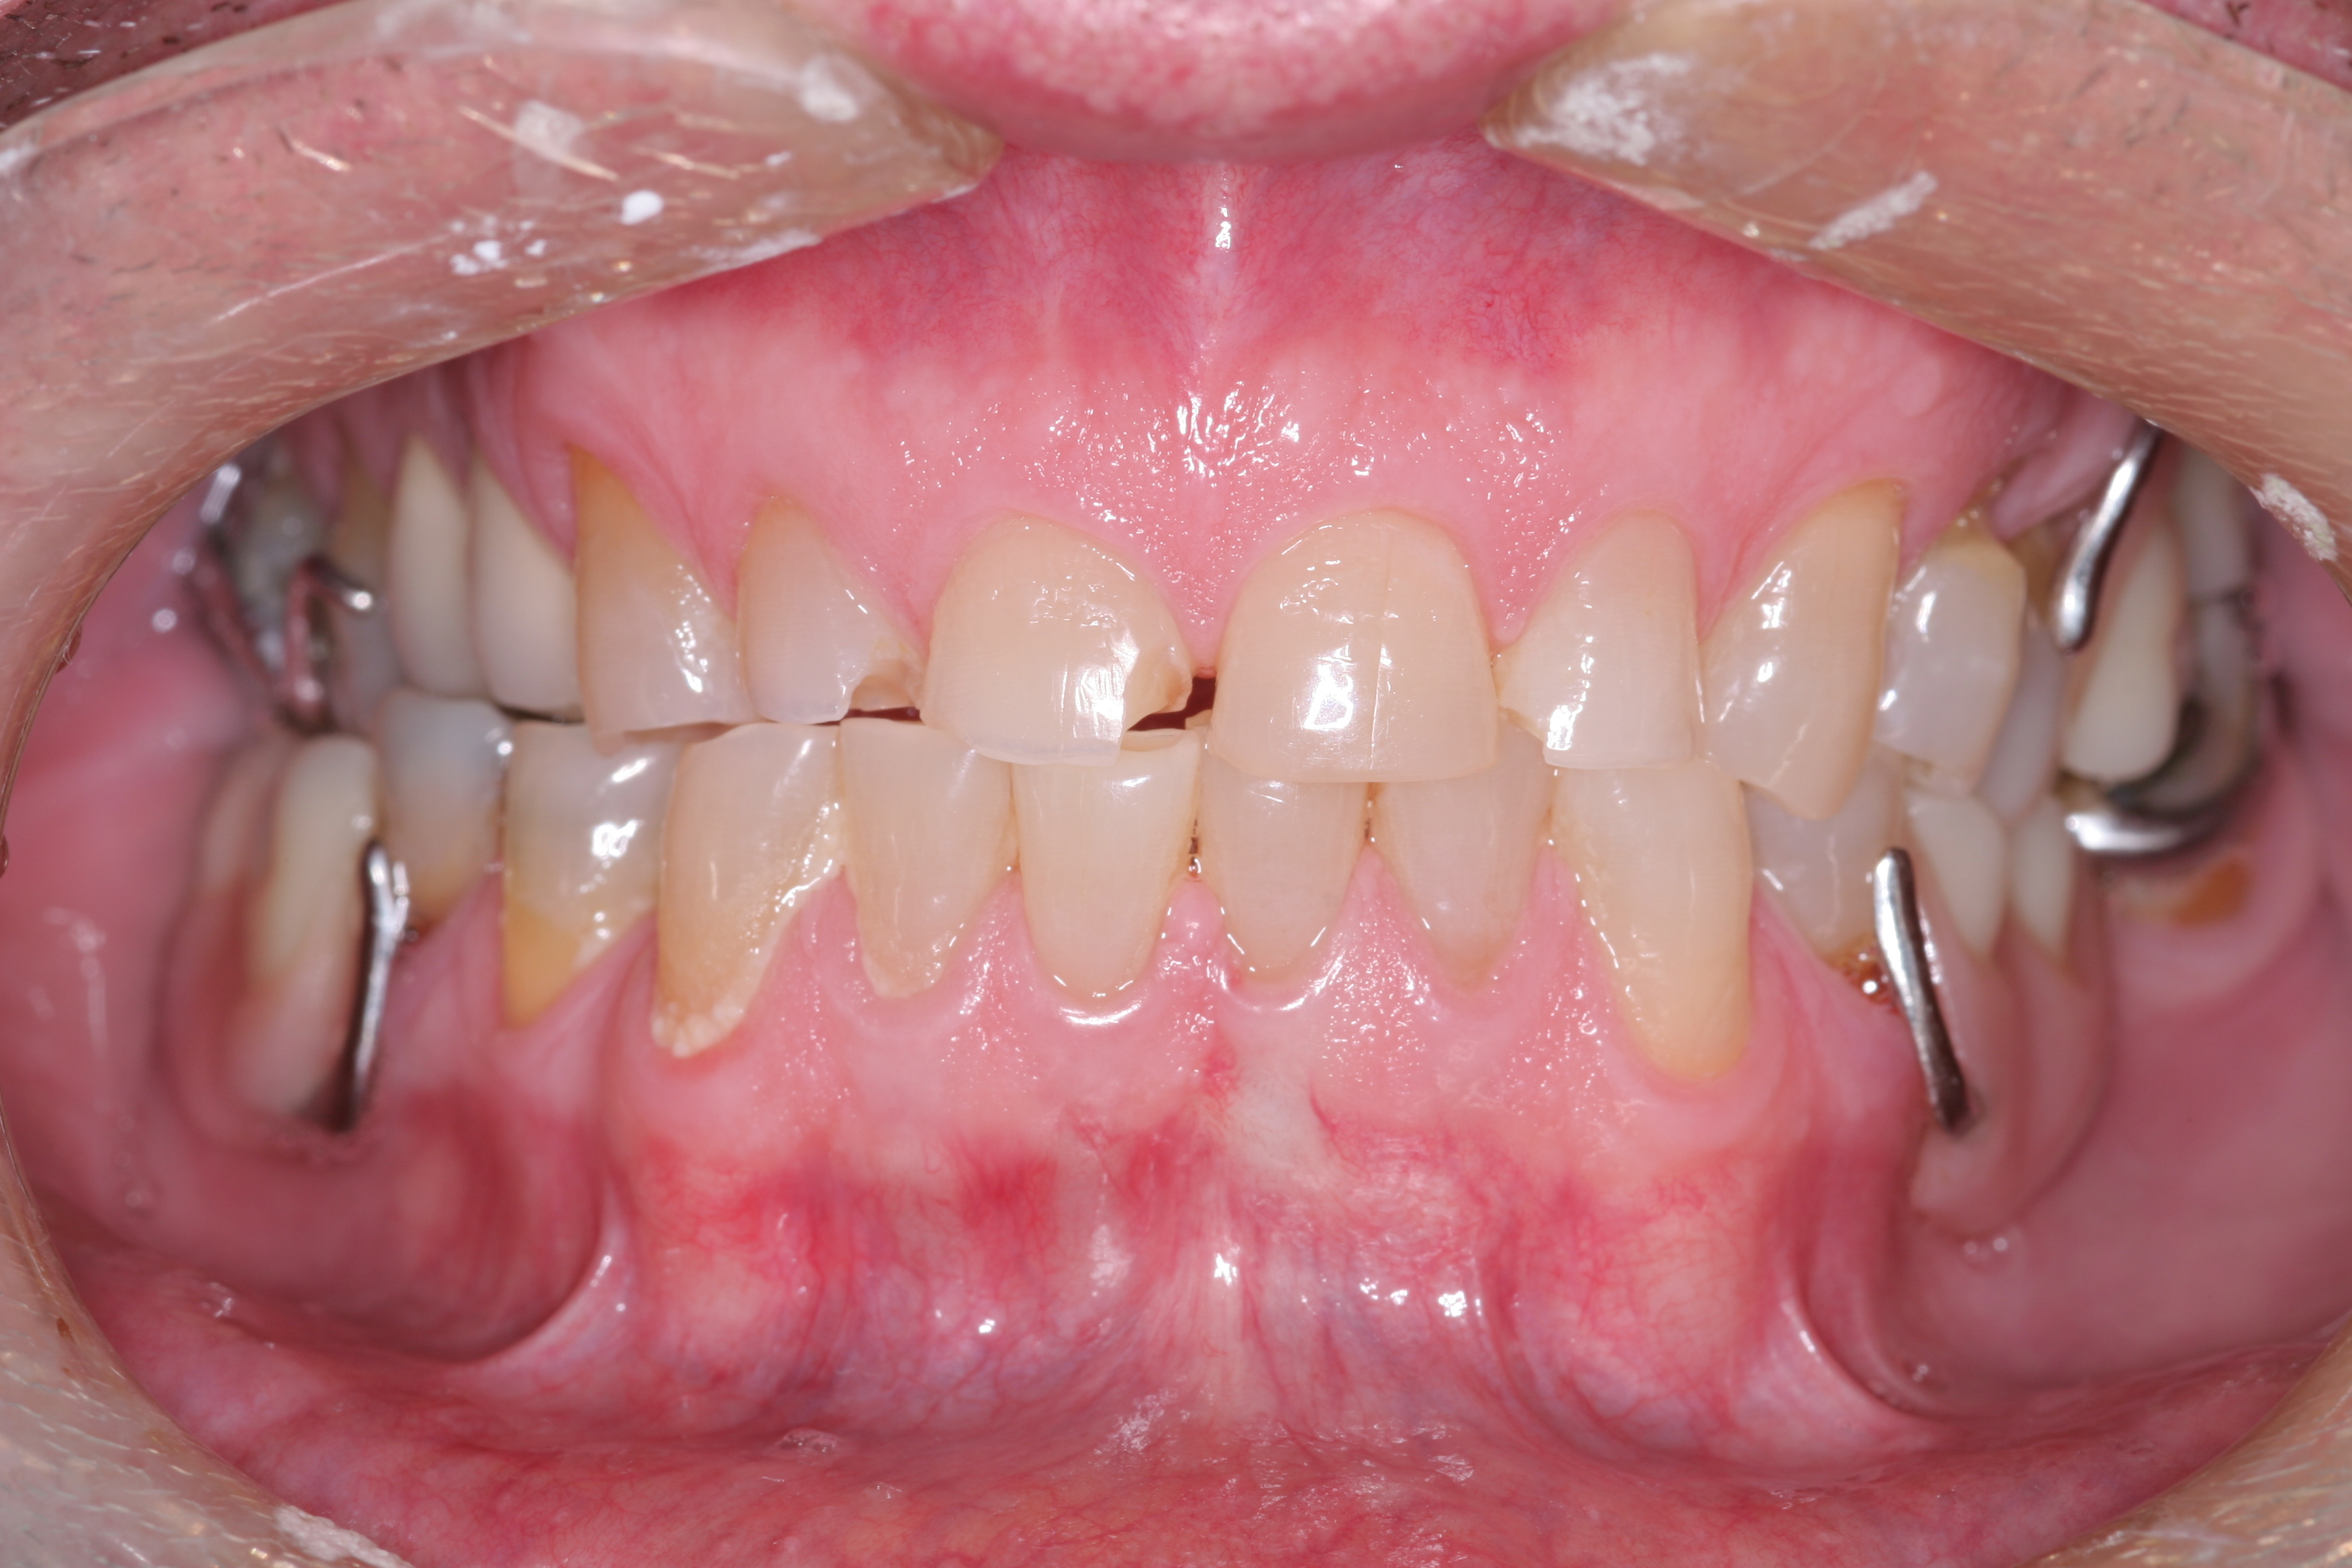

A patient presented with advanced generalized wear of her anterior teeth (Figure 10 and Figure 11). She was displeased with their overall appearance because of their color and wear (Figure 12). A complete examination was performed, revealing instability in her temporomandibular lateral poles bilaterally, sore muscles of mastication, advanced wear, a CR/MIP discrepancy, and loss of her anterior guidance due to the wear. Although the topic is beyond the scope of this article, the patient was also screened for possible sleep apnea. This included an evaluation of the Mallampati score, previous sleep therapy evaluation or treatment, snoring history, an evaluation of her neck size, her weight status, and the presence of the tonsils and their size. In every case, if this clinician suspects airway obstruction to be playing a role in tooth wear issues, the patient is referred to a sleep physician. The patient in this case displayed few apnea risk factors, and the patient’s anterior wear facets fit together like a “lock and key” pattern seen in parafunctional activity. Splint therapy was initiated to stabilize the joints and muscles. A repeatable CR position was verified through load testing. At this point diagnostic models, photographs, a CR bite record, and a facebow were taken and recorded.

(10.) A patient presented with advanced generalized wear of her anterior teeth, and was displeased with their overall appearance because of their color and wear.

Figure 10

(11.) A patient presented with advanced generalized wear of her anterior teeth, and was displeased with their overall appearance because of their color and wear.

Figure 11

(12.) A patient presented with advanced generalized wear of her anterior teeth, and was displeased with their overall appearance because of their color and wear.

Figure 12